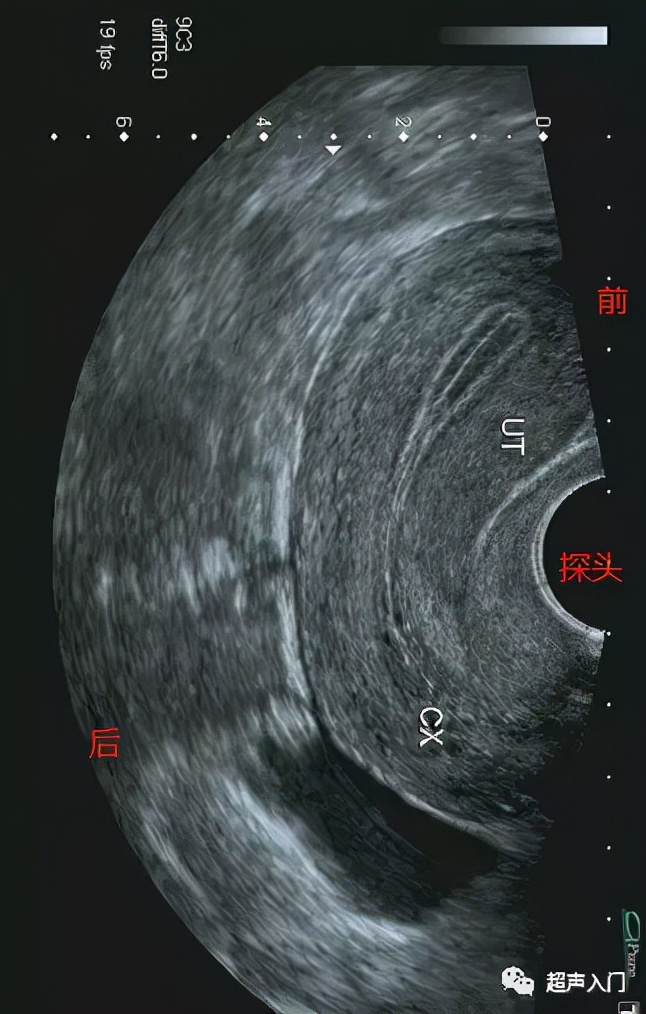

经阴道超声又如何分前后壁呢?

其实是一样的分发,离腹壁近的是前壁,如离背侧近的是后壁,只不过在阴道超声很多小伙伴不知道如何分前后左右了!

首先,你得明白阴超成像方式。

旋转后的图像